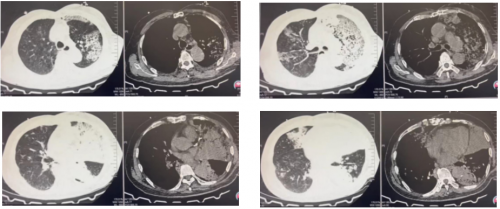

胸部CT检查:

双肺多发斑片影,左肺为著,纵隔内未见肿大淋巴结影,主动脉及冠状动脉硬化,胸部术后改变。

2.本次因发热伴咳嗽、咳痰入院,体温最高值不详,咳嗽,痰液不易咳出,就诊于外院肺CT提示双肺多肺叶感染性病变、左肺明显。